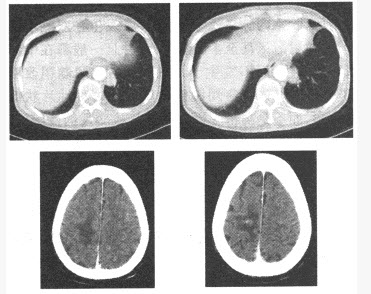

(单选题)该患者的CT所示,结合病史,该患者最可能的诊断是()

A:肺脓肿

B:肺癌

C:炎性假瘤

D:肺结核

E:转移瘤

F:大叶性肺炎